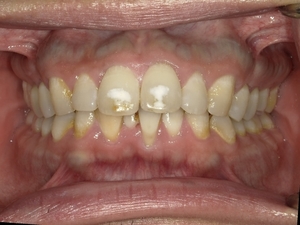

ガタガタとした歯並びや八重歯(叢生)CASE74